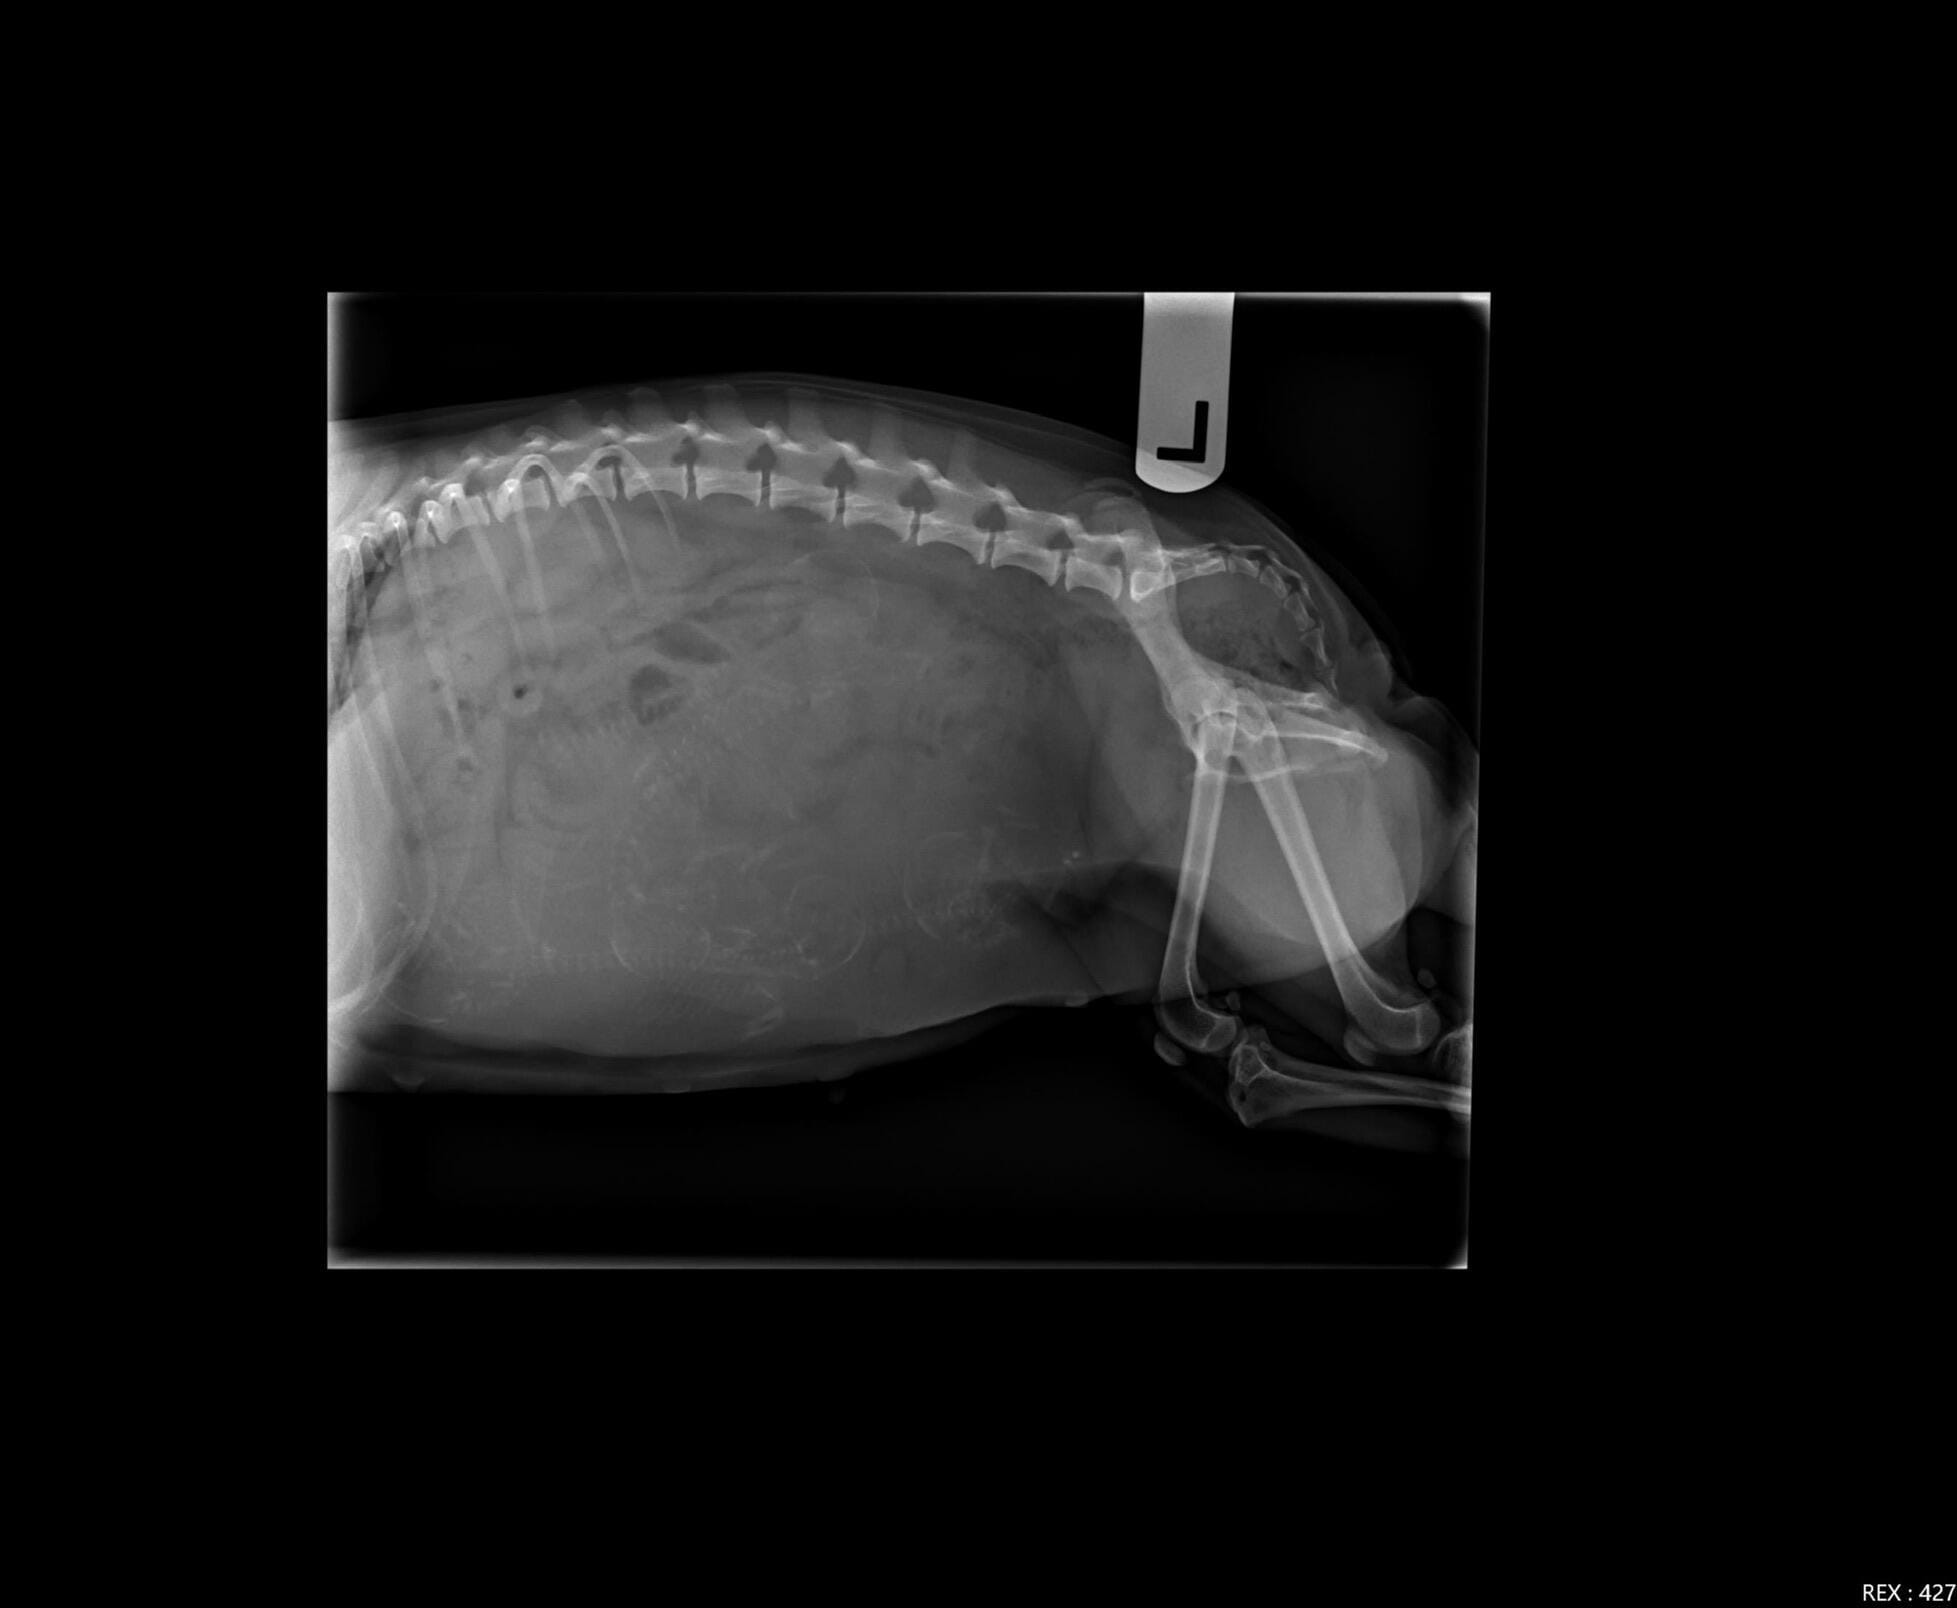

My Chihuahua is on her 57th day, her temperature is 99.8. Should we spect her to have the puppies (she is having having 6) in the next 24 hours? She is no panting or “nesting” just yet, but walking around and following me more than usual today. She is been pretty much sleeping all her pregnancy. Her appetite is really picky but now is worst. Should I be concern ?

Changes in appetite and temperature can indicate labor is close. If she's had a litter before, second and beyond litters will often be closer to 60 days than 63-65, so it is possible she is very close to her due date. I would continue to monitor her, and if she doesn't seem to be progressing to labor (contractions, nesting, waxing of nipples, etc) or seems to be in great distress, have her checked by your vet to make sure there isn't another cause, especially since she is having such a large litter for her size!